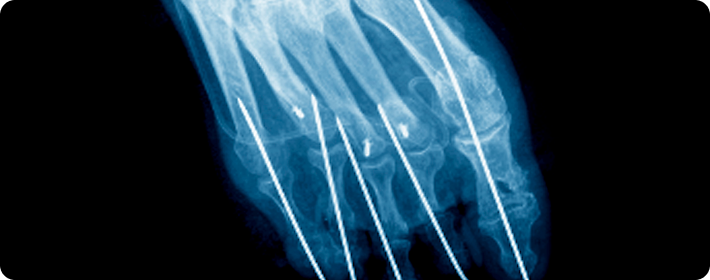

활차 유리술

손가락 힘줄을 둘러싼 활차(힘줄이 통과하는 섬유띠)를 절개하여 치료하는 수술입니다. 힘줄이 원활히 움직이도록 눌린 부위를 풀어 손가락의 통증과 움직임 장애를 개선합니다.